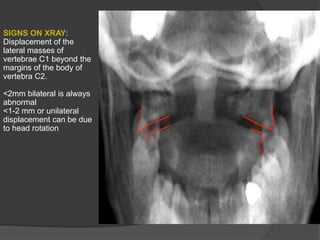

SIGNS ON XRAY:

Displacement of the

lateral masses of

vertebrae C1 beyond the

margins of the body of

vertebra C2.

<2mm bilateral is always

abnormal

<1-2 mm or unilateral

displacement can be due

to head rotation